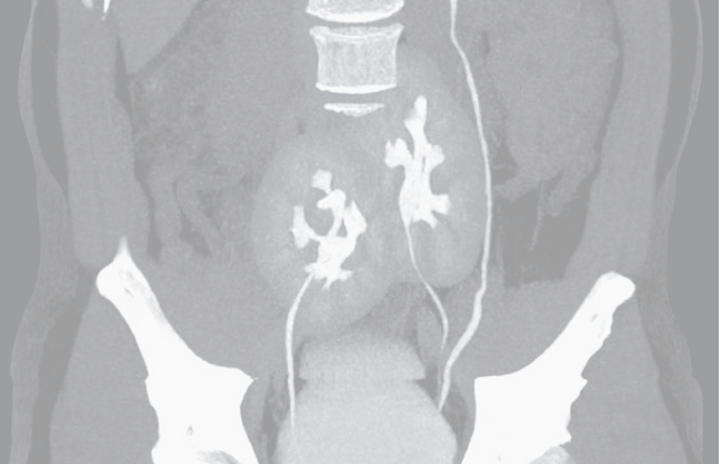

Los expertos que lo atendieron hablaron sobre el hallazgo en The New England Journal of Medicine. Al atender al paciente de 38 años para entender las causas del dolor, le realizaron una tomografía computarizada.

Para su asombro, en las imágenes encontraron que además de una hernia discal en la región lumbar, tenía también tres riñones en lugar de dos.

Uno de los riñones tenía forma y tamaño normal y estaba ubicado a la izquierda, en tanto que los otros dos estaban fusionados en forma de herradura y ubicados mucho más abajo, cerca de la zona de la pelvis.